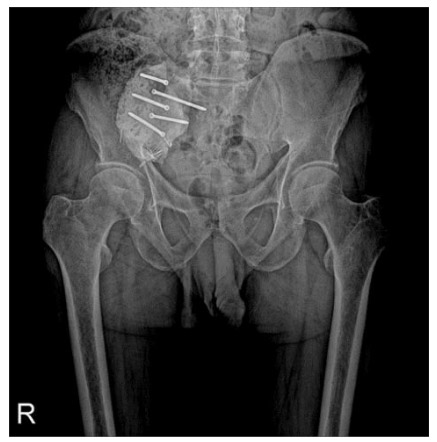

Post-Surgery: Bone cement secured with screws in the right sacroiliac joint.